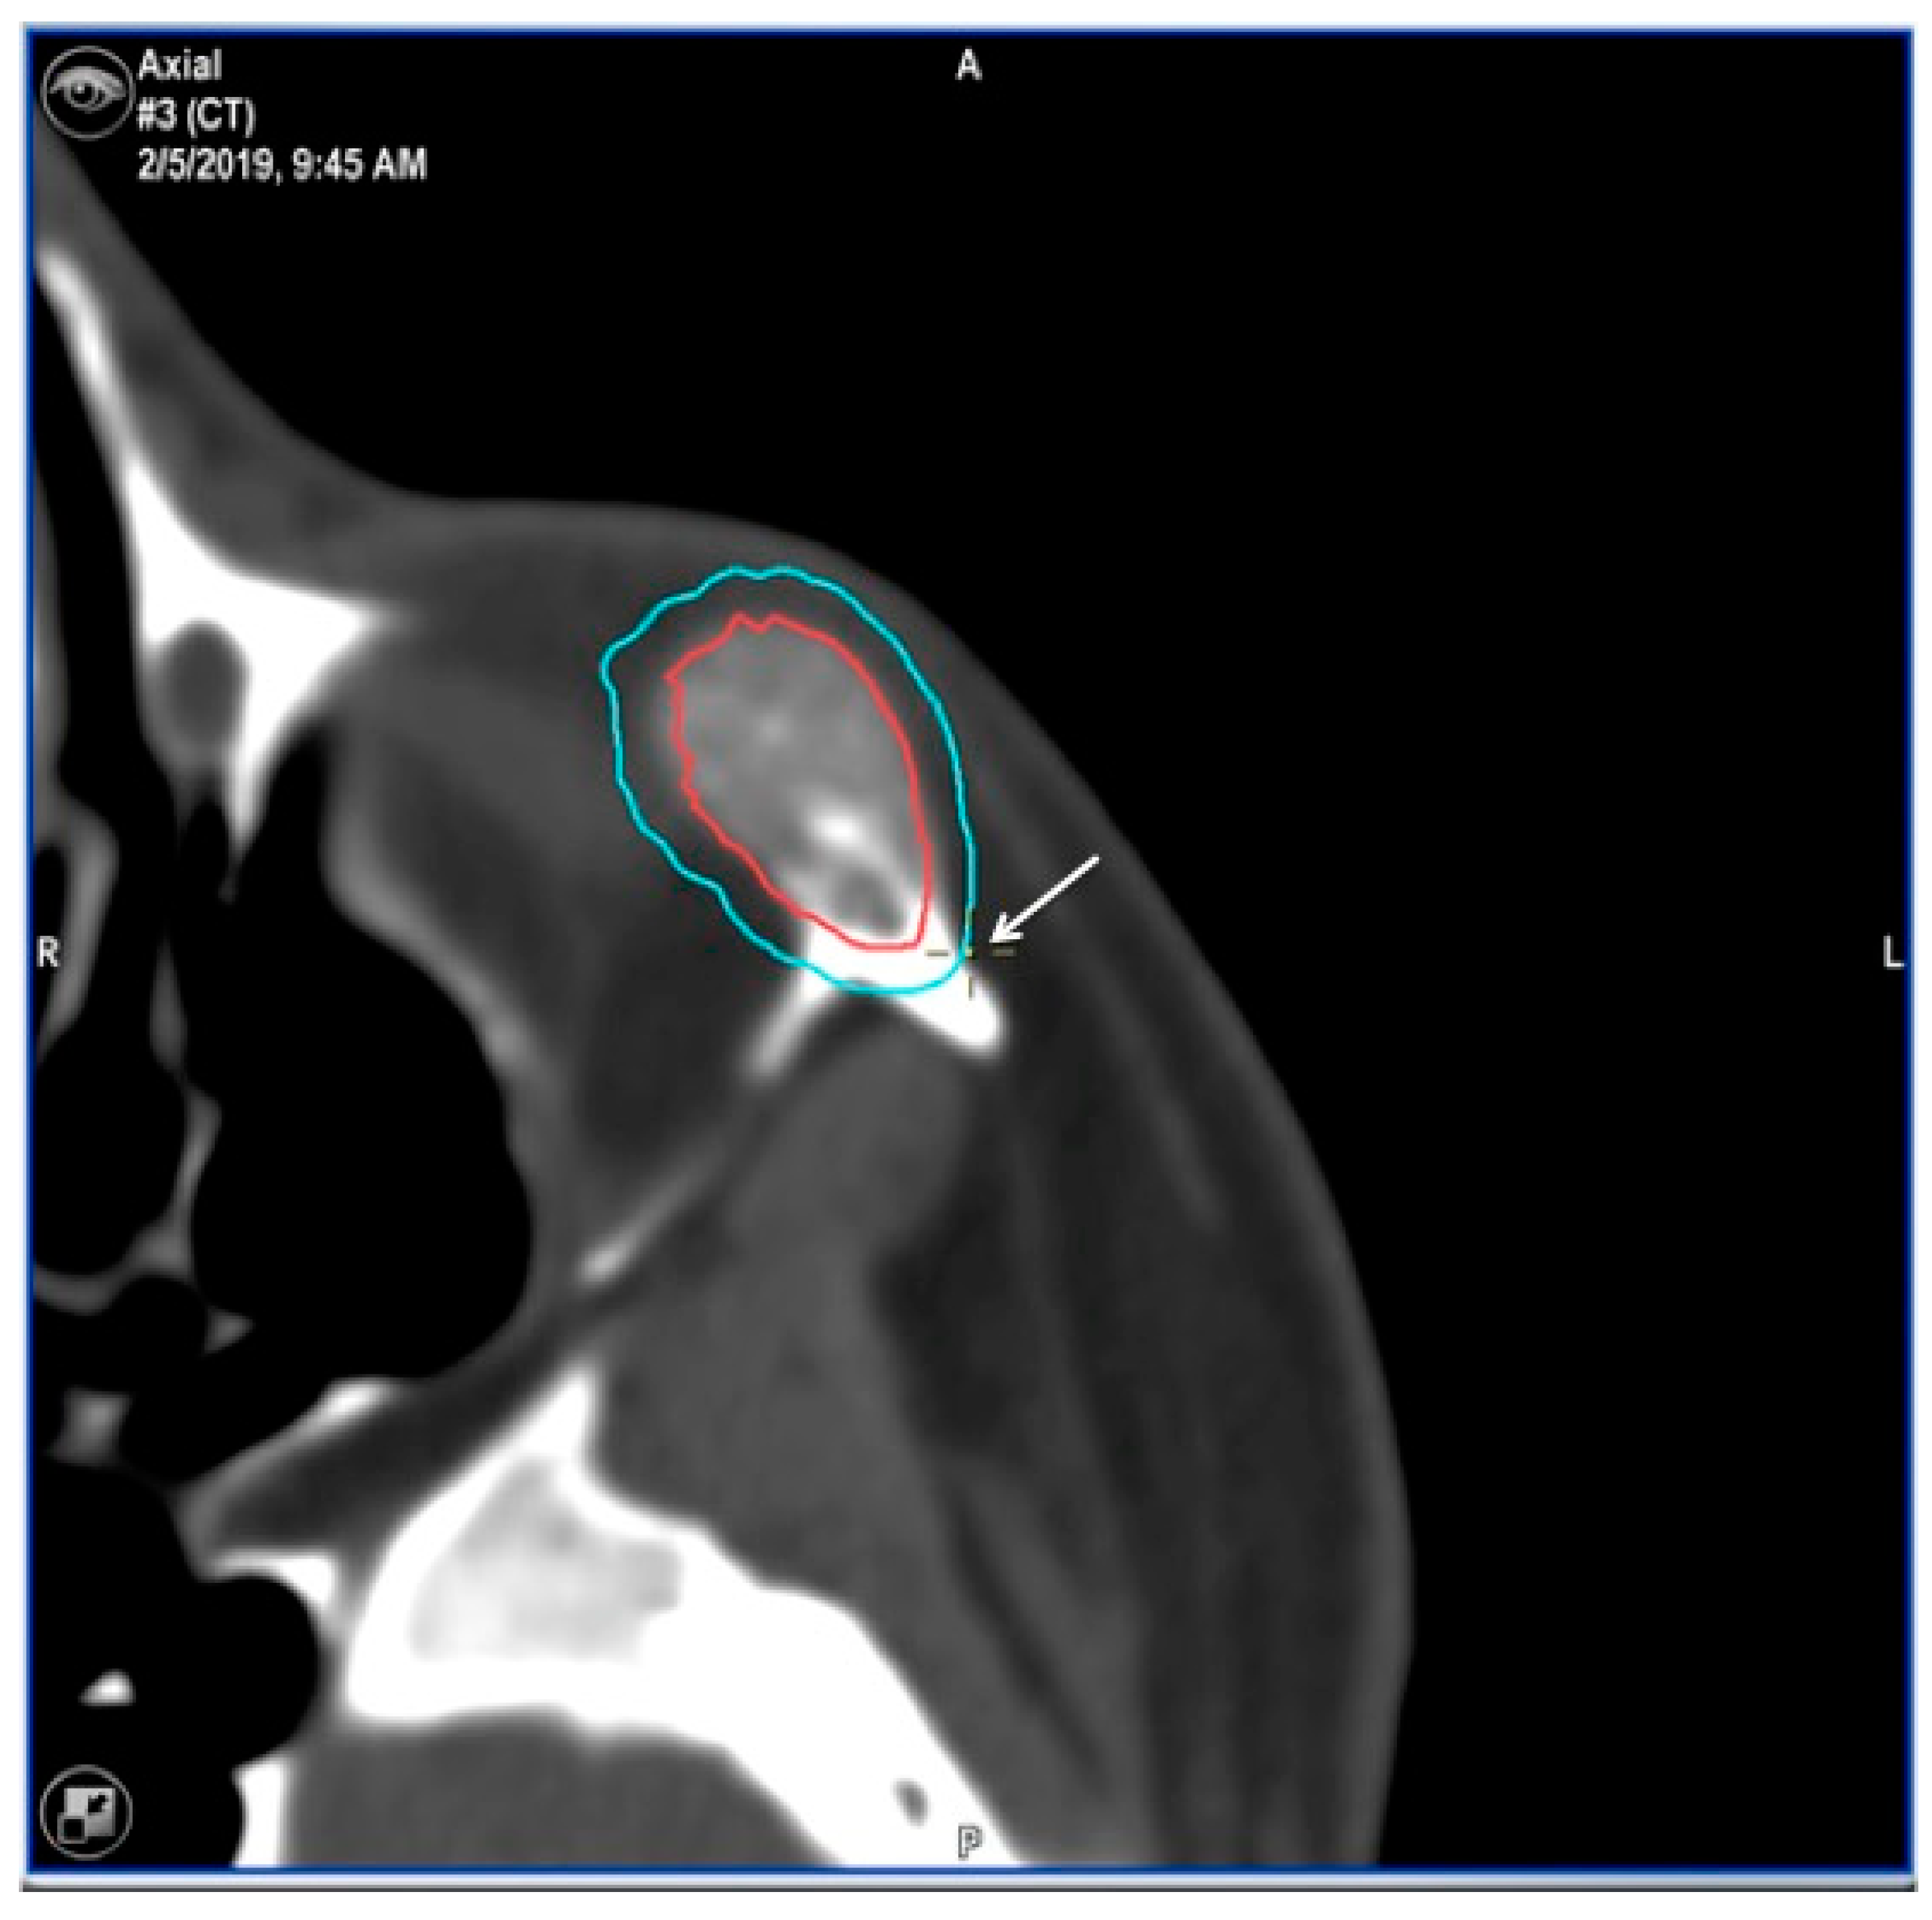

2.3.1. Virtual Surgical Plan

2.3.2. CAD-CAM Design of the PEEK Prosthesis

2.3.3. Surgical Navigation